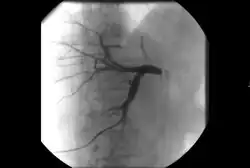

Takayasu arteritis angiography